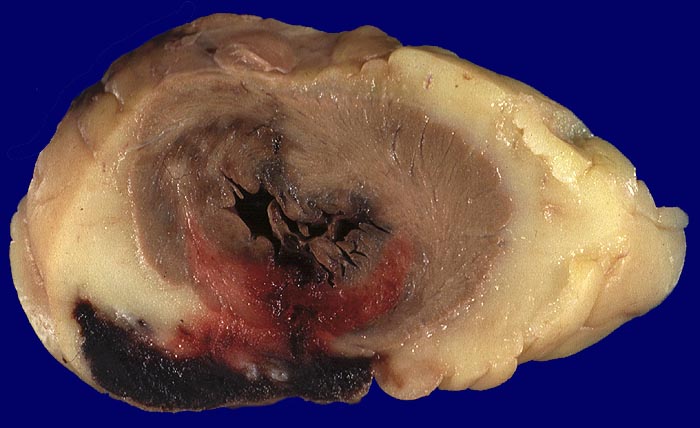

Akuter Myokardinfarkt des Septums mit Ruptur

Formalinfixiertes Gewebe. Myokardquerschnitt durch die transmurale Rupturstelle spitzennah. Blutaustritt in das epikardiale Fettgewebe.